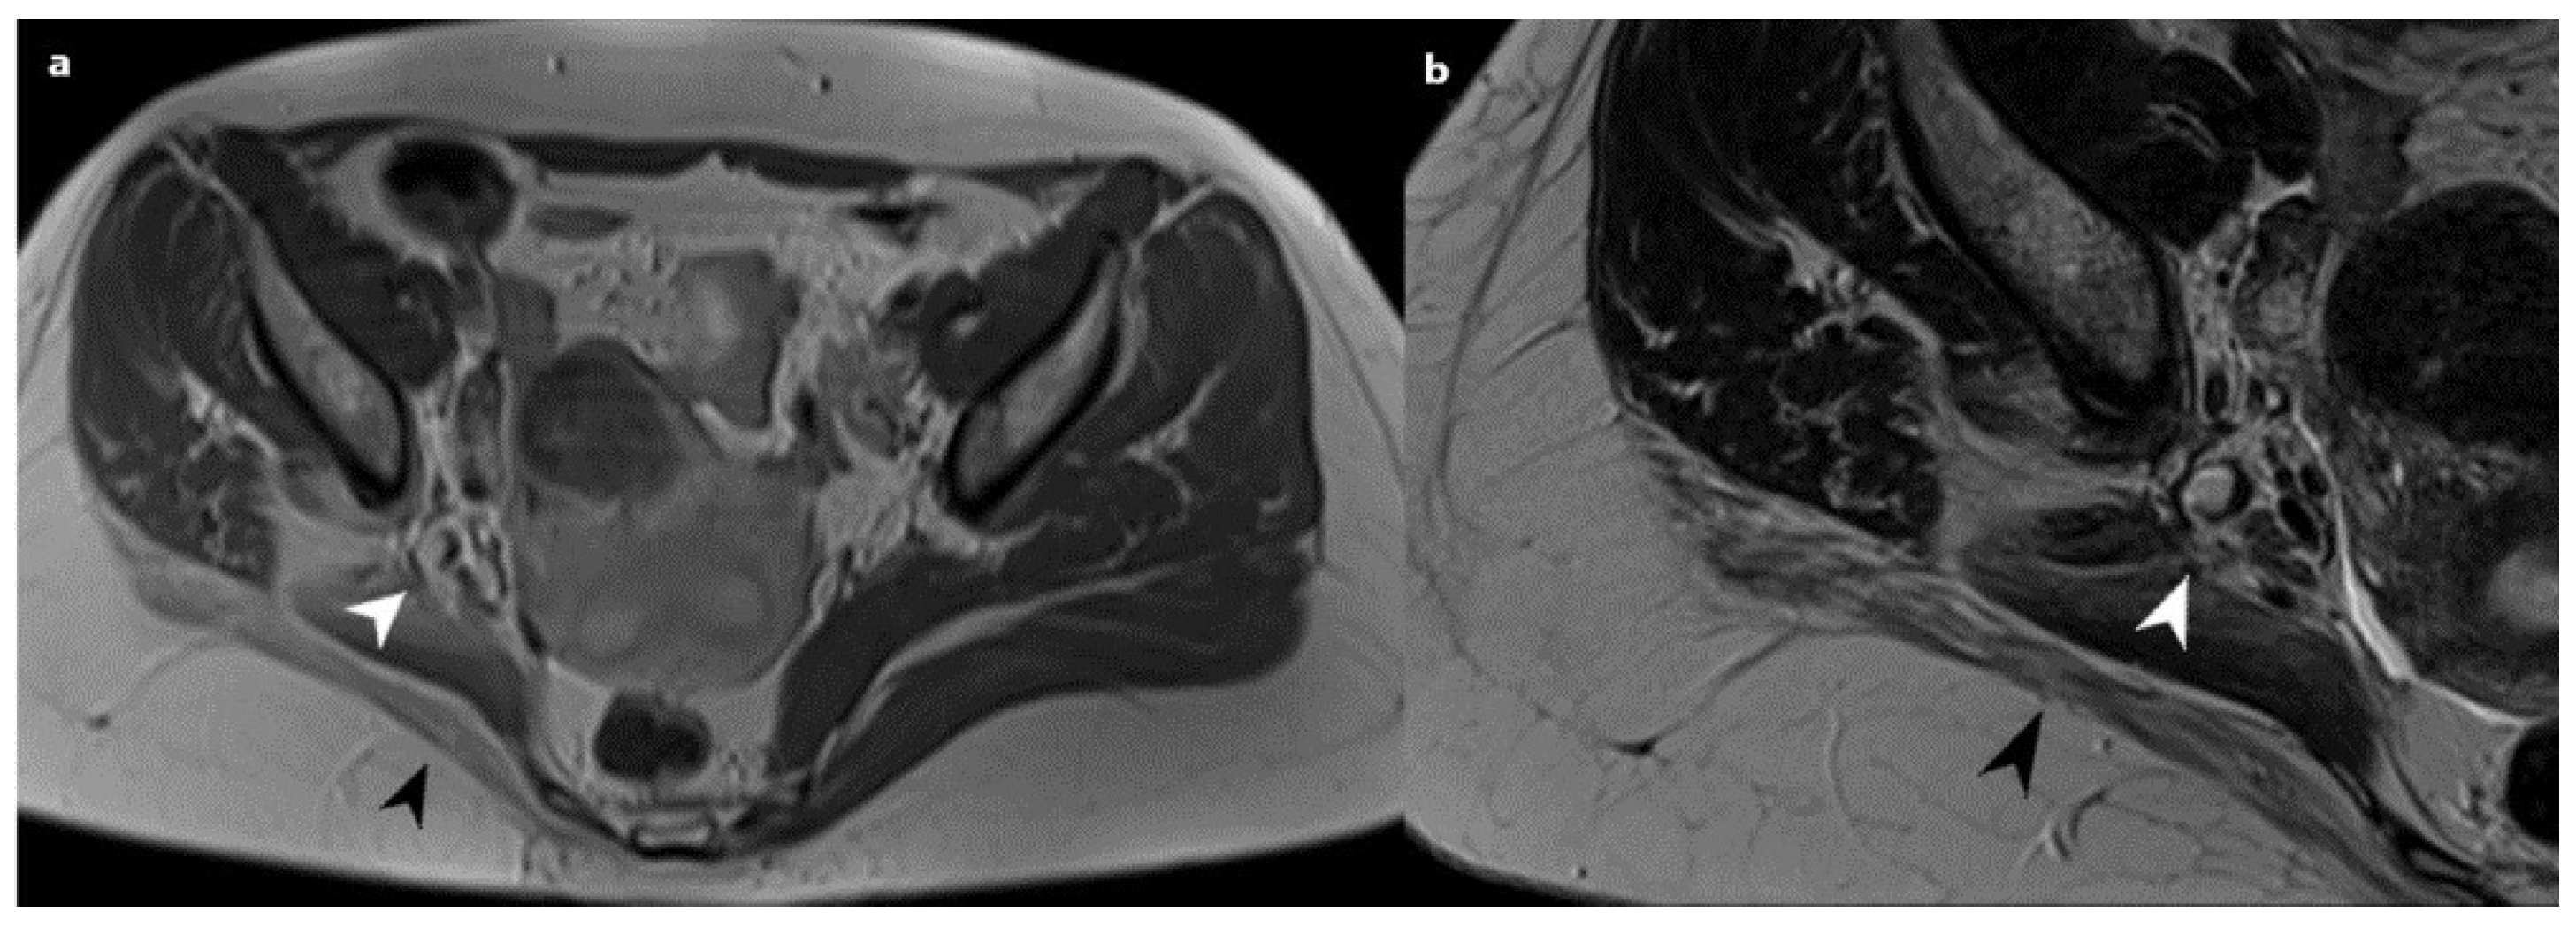

Based on the histological observations indicating the presence of endometriosis in the sciatic nerve, the patient was subsequently sent to a gynecologist for a follow-up examination and the prescription of appropriate treatment. The patient was recommended to initiate treatment with GnRH analogs (Triptorelin 3.75 mg) for 6 months (6 cycles) and then to return for a repeat examination. On the 6-month follow-up, the patient confirmed that she tolerated the treatment with GnRH analogs well. After the completion of GnRHa treatment, a follow-up hormonal status and MRI were performed. Scans revealed alterations in the right sciatic nerve, characterized by increased thickness in the proximal segments, with subsequent piriform muscle fatty atrophy. The right ischiatic nerve was observed to be attached to a now reduced-sized endometriosis nodule, visible as a hyperintense zone measuring 7 mm. (Figure 3). Right gluteal muscle group atrophy persisted. In addition to the observed alterations in the DIE lesion and the sciatic nerve, no significant differences were observed when comparing the pre-biopsy MRI scans.

Figure 3. Post-GnRHa treatment; an axial T1 (a) and T2 (b) weighted MRI scan showing a now reduced-sized right sciatic endometriosis nodule (white arrowheads); note gluteal muscle atrophy (black arrowheads).